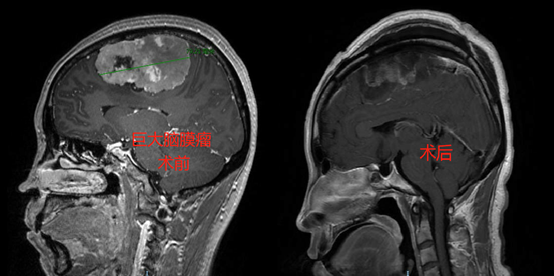

看看我们近期收治的几例良性肿瘤患者,您还敢不做颅脑的体检嘛?

7.闭经泌乳,不孕不育。育龄妇女非妊娠的闭经、泌乳常为垂体肿瘤的首发症状。男性主要表现为阳痿和阴毛、腋毛、胡须脱落、皮肤细腻等。出现上述症状不要只就诊于妇科或男科哟,说不准是大脑的事儿呢。

8.肥胖、肢端肥大、样貌变丑、不明原因的三高、睡眠呼吸暂停。这也可能是垂体瘤的首发症状。